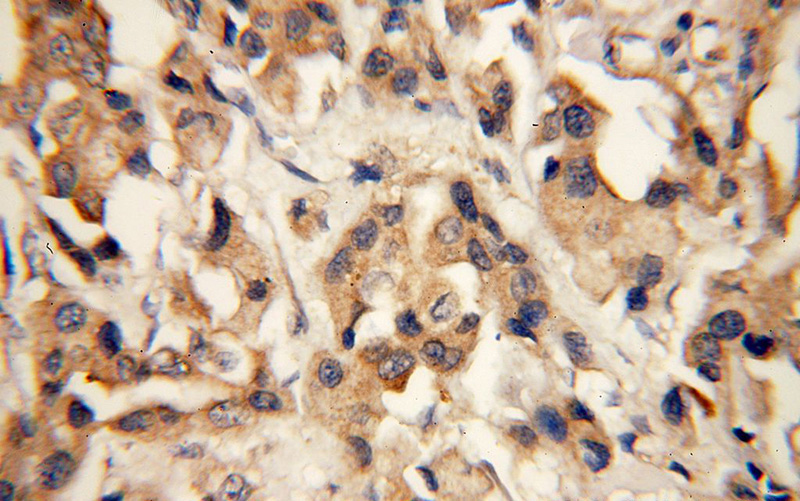

SH3PXD2A Rabbit Polyclonal antibody. Positive IHC detected in human breast cancer tissue. Positive IF detected in HepG2 cells. Positive WB detected in HeLa cells, HepG2 cells. Observed molecular weight by Western-blot: 140-150 kDa

Immunohistochemical of paraffin-embedded human breast cancer using Catalog No:115262(SH3PXD2A antibody) at dilution of 1:50 (under 40x lens)

SH3PXD2A is also named as FISH, KIAA0418, SH3MD1, TKS5. SH3PXD2A contains an amino-terminal PX domain followed by five SH3 domains. It is a cytoplasmic protein in normal fibroblasts(PMID:19464300).The p140 and p130 forms of SH3PXD2A may be generated by other splice variations. The complexity of SH3PXD2A isoforms is also evident in different cell types. For example in human platelets a single band of 150kDa was detected, whereas all three forms were found in human fibroblasts and vascular smooth muscle cells(PMID:9687503).This antibody is specific to SH3PXD2A.